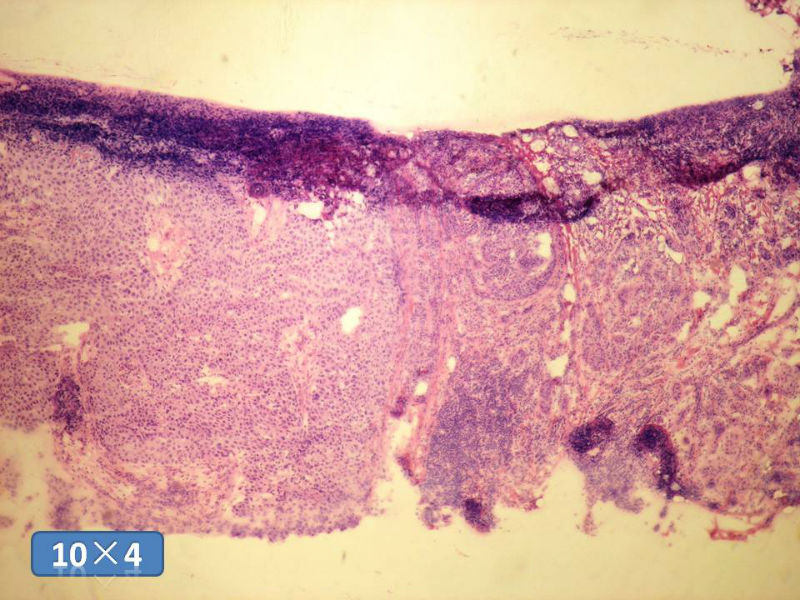

女性,50岁,乳腺肿物,冰冻切片(图1-25)

HE